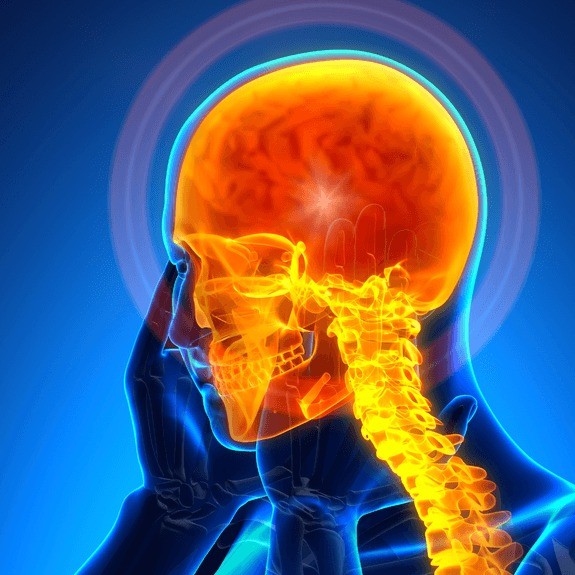

Microvascular decompression is brain surgery to remove pressure (decompression) caused by a very small blood vessel (microvascular) on a cranial nerve, usually the trigeminal nerve.

Candidates for microvascular decompression surgery tend to be younger patients (under age 65) with glossopharyngeal neuralgia, hemifacial spasms or trigeminal neuralgia not caused by multiple sclerosis. Microvascular decompression may be an option if medications and other conservative care treatments have failed to provide relief.

A microvascular decompression surgery usually provides immediate relief of the facial pain or facial twitches.